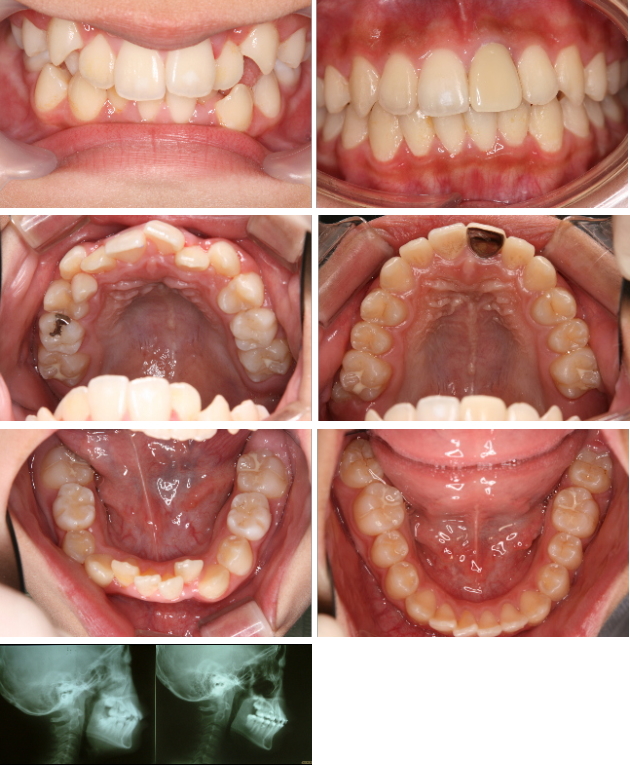

2011年10月19日 / 最終更新日時 : 2019年5月18日 藤井歯科医院 矯正治療の症例 中学生の歯を抜かない全顎矯正症例(期間1年半) 13歳の男の子です。全体に歯がガタガタしています。 歯にボタン(ブラケット)を接着して、針金を使って矯正しました。 期間は1年半です。 左が矯正前、右が矯正終了時です。